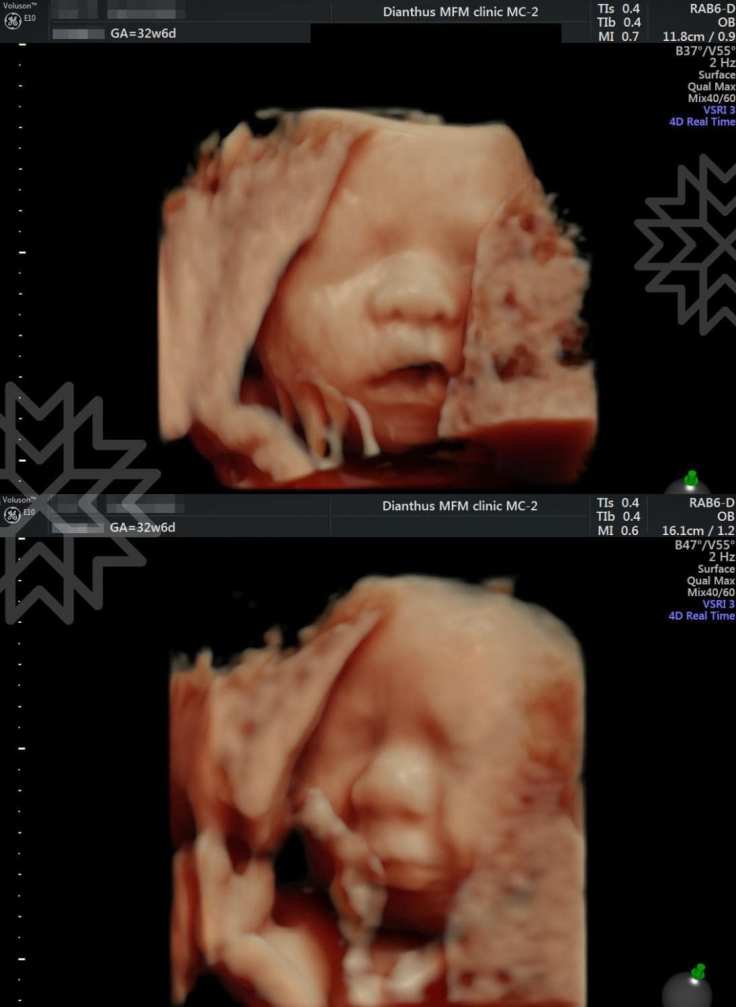

今天來聊聊高層次超音波

而高層次超音波或進一步的心臟超音波的目的

就是盡早讓我們發現敵人在哪裡

而不會讓我們措手不及